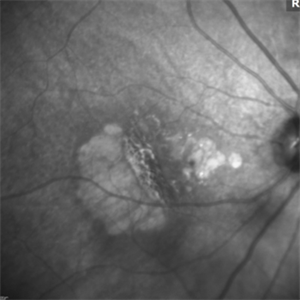

RPE Tear: Autofluorescence

Autofluorescence image: Note the discrete hypo-autofluorescence due to the absent RPE temporally. Note also the hypo-autofluorescence due to geographic atrophy centrally.

Photographer: Stuart Alfred

Condition/keywords: choroidal neovascular membrane (CNVM), retinal pigment epithelium (RPE) tear, wet age-related macular degeneration (wet AMD)